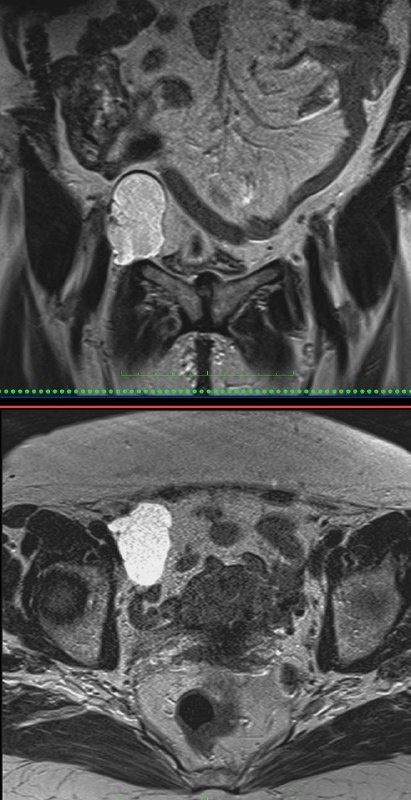

Женщина 87 лет, исследование проводилось по поводу кровянистых выделений из половых путей и наличия крови в моче, помимо недостаточности мышц тазового дна и опущения мочевого пузыря, мочеиспускательного канала, влагалища и прямой кишки было обнаружено светящееся пятно справа походу наружных подвздошных сосудов на диффузии. Так как было проведено ещё дополнительно динамическое исследование с контрастом, было доказано наличие венозного подвздошно-бедренного тромбоза. Кривая время-интенсивность на наружной подвздошной Вене представляет собой прямую (небольшие неровности не в счет, это из-за артефактов). Интересно, что это её никак не беспокоит. Видимо, всё компенсировано, на удивление.